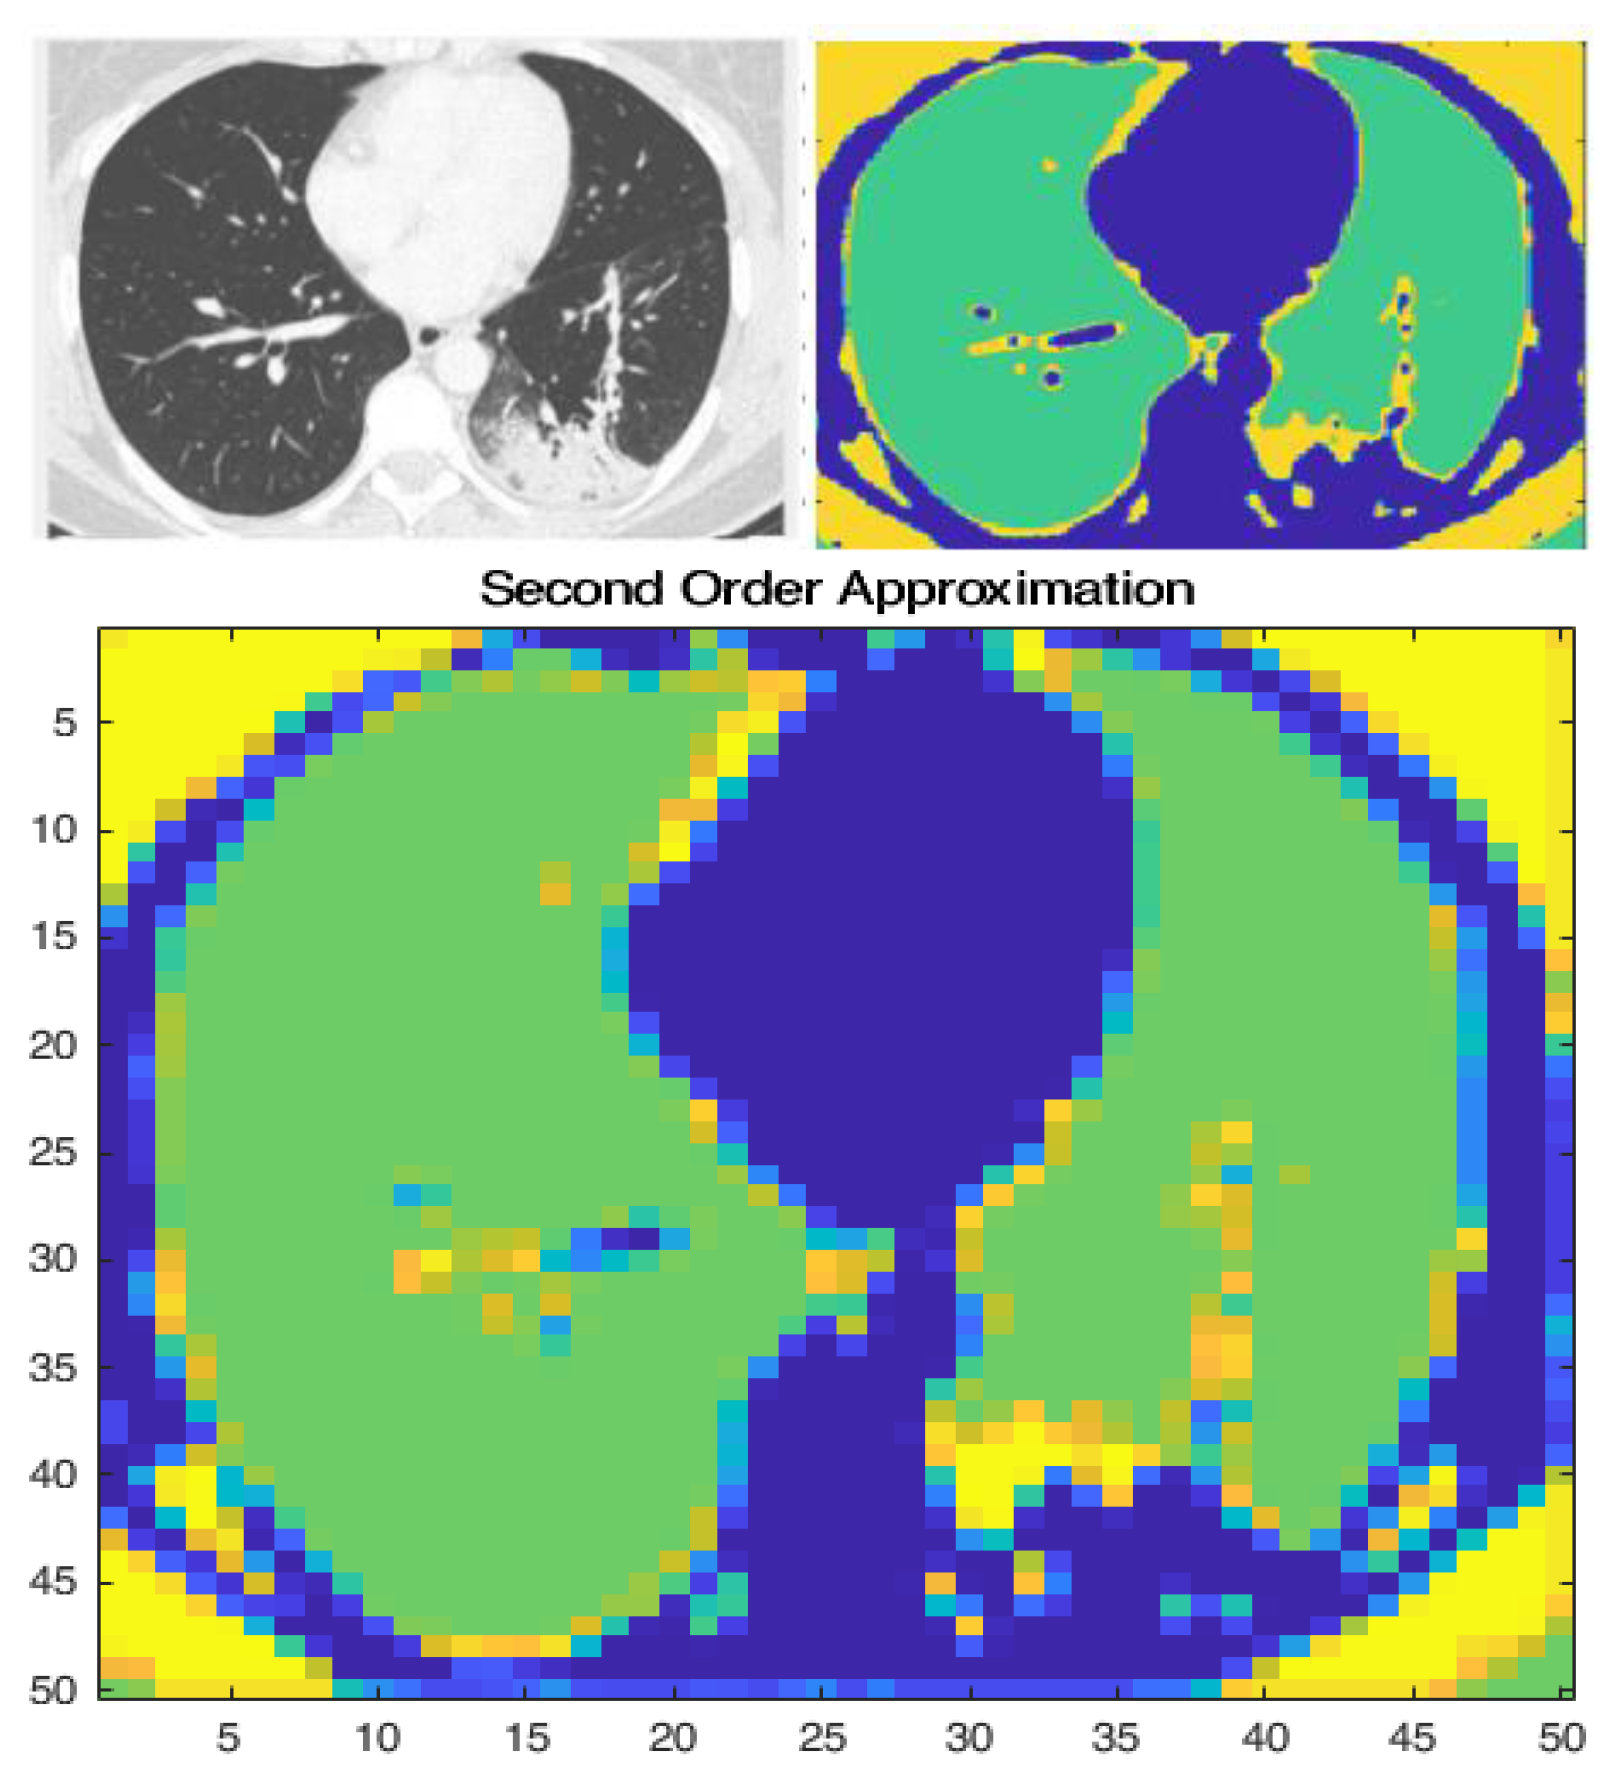

The RGB index image in Figure 6 shows the previously mentioned multiple thresholding technique, which is separated into three parts and the areas of consolidation are marked as the yellow sections. The primary objective for the Haar Wavelet transformation was to reduce the overall dimensions whilst retaining the most important data. By implementing the first and second-order derivation, Figure 6 (bottom plot) shows the difference in the features retained. The second-order derivation was used as a benchmark for its efficacy as a feature map.

Figure 6. Original and Filtered Image (top) and second-order approximation of wavelet transform (bottom).